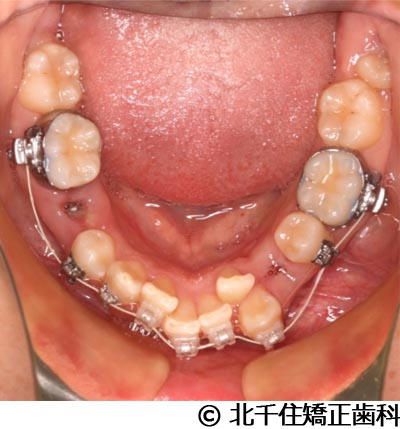

【症例2】上顎前突症

- 治療前

- 治療中

- 治療後

- 治療名

- 上顎前突症

- 費用

- 1,399,000円(税込)

- 期間

- 3年6ヵ月

- 治療回数

- 42回

- 通院頻度

- 1ヵ月ごと

- 年齢・性別

- 19歳10ヵ月・男性(初診時)

主訴:出っ歯、口元の突出、横顔をきれいにしたい

骨格性の上顎前突、上下顎第一小臼歯4本及び上顎第二大臼歯を抜歯して矯正用アンカースクリューを併用してワイヤー矯正治療(セラミックブラケット)。

骨格性上顎前突に対し、抜歯および矯正用アンカースクリューを併用した矯正治療により歯列および咬合関係の調整を行った症例である。治療後は保定装置を使用し、歯列および咬合の安定維持を目的として定期的な経過観察を行っている。

※治療結果は個人差があります。

治療を行う上での注意点(リスク・副作用)

歯磨き不良に伴うカリエスや歯周病、顎関節症、歯根吸収など。